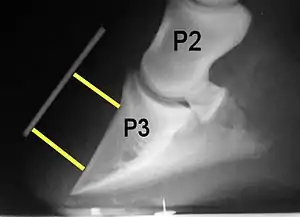

Radiograph of a horse hoof showing rotation of the coffin bone and evidence of sinking, a condition often associated with laminitis. The annotation P2 stands for the middle phalanx, or pastern bone, and P3 denotes the distal phalanx, or coffin bone. The yellow lines mark the distance between the top and bottom part of the coffin bone relative to the hoof wall, showing the distal (bottom) of the coffin bone is rotated away from the hoof wall.

Rotation, sinking, and founder

Normally, the front of the third phalanx is parallel to the hoof wall and its lower surface should be roughly parallel to the ground surface. A single severe laminitic episode or repeated, less severe episodes can, depending upon the degree of separation of dermal and epidermal laminae, lead to either rotation or sinking of the pedal bone, both of which result in anatomical changes in the position of the coffin bone with visible separation of the laminae, colloquially known as founder. Rotation and distal displacement may occur in the same horse.[4] Both forms of displacement may lead to the coffin bone penetrating the sole. Penetration of the sole is not inherently fatal; many horses have been returned to service by aggressive treatment by a veterinarian and farrier, but the treatment is time-consuming, difficult and expensive.

Rotation is the most common form of displacement, and, in this case, the tip of the coffin bone rotates downward.[4] The degree of rotation may be influenced by the severity of the initial attack and the time of initiation and aggressiveness of treatment. A combination of forces (e.g. the tension of the deep digital flexor tendon and the weight of the horse) result in the deep digital flexor tendon literally pulling the dorsal face of the coffin bone away from the inside of the hoof wall, which allows the coffin bone to rotate. Also, ligaments attaching the collateral cartilages to the digit, primarily in the palmar portion of the foot, possibly contribute to a difference in support from front to back. The body weight of the animal probably contributes to rotation of the coffin bone. Rotation results in an obvious misalignment between PII (the short pastern bone) and PIII (the coffin bone). If rotation of the third phalanx continues, its tip can eventually penetrate the sole of the foot.